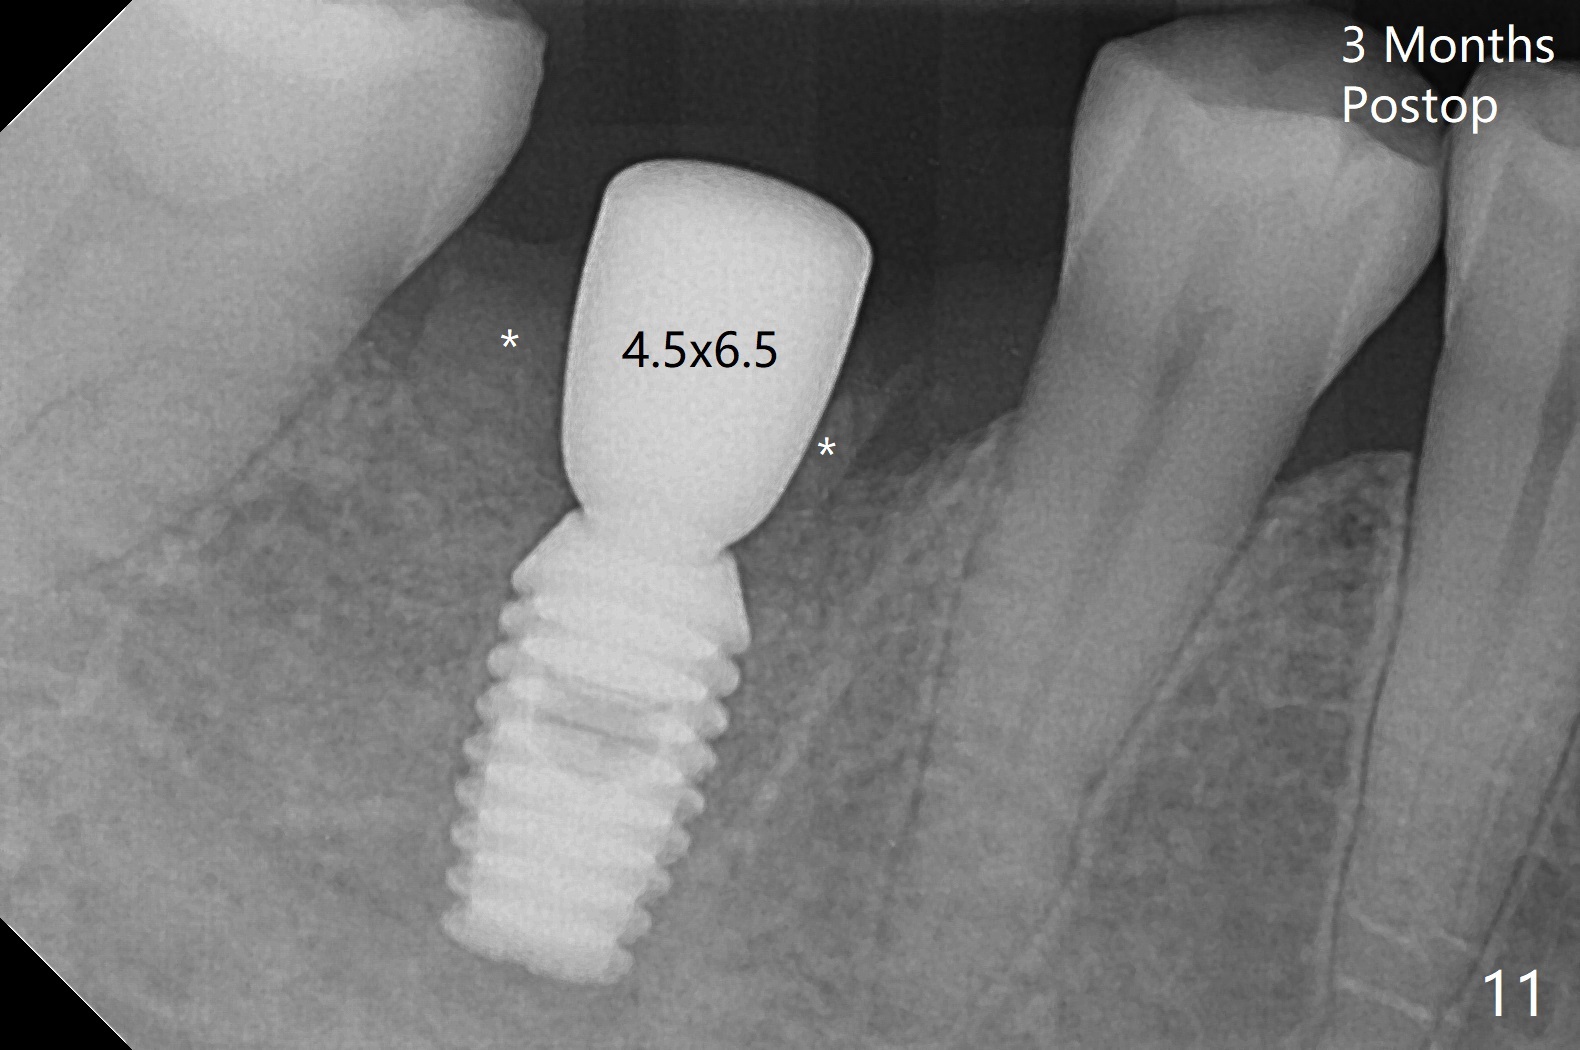

To prevent further postop buccal gingival recession at #30, socket shield is formed with removal of the residual roots (Fig.1,2 *). Osteotomy is initiated in the septum (Fig.2 S, to be flattened with bone trimmer and surgical round bur) and gradually slides slightly into the mesial socket in spite of using surgical guide (Fig.3 *: sleeve). Following 4.5x11.5 mm drill, a 4.5x8 mm Bicon implant is pressed fit; its stability is lightly enhanced with placement of sticky bone in the remaining sockets (Fig.4 *) and around the black plug (Fig.5 P). After removing the coronal portion of the plug to reduce occlusal interference, two pieces of PRF are wrapped around the remaining plug (Fig.6). The main stability of the implant is obtained when setting acrylic (A in Fig.7) is applied into the edentulous space (undercut). After acrylic setting, flowable composite (*) is added distal for further retention. One month postop, the flowable composite is detached. The provisional is sectioned; the black plug is cut. The socket heals with exposure of the mesial socket shield (Fig.8 >). The black healing plug and the mesial socket shield remains exposed 3 months postop (Fig.9). When a 4.5x6.5 mm temporary abutment is placed, the buccal gingiva is blanched and the mesial socket shield is pushed buccal (Fig.10). The implant appears to remain covered by the bone 3 months postop (Fig.11). Cortical bone starts to form crestal 7 months postop (Fig.12 arrowheads, coronavirus). The cortex seems to thicken 8 months postop (Fig.13 *).